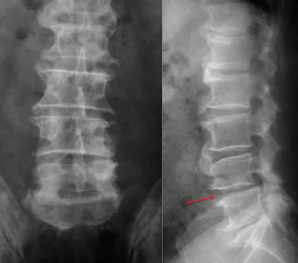

🦴 2. 腰椎骨刺(腰椎退化性關節病)

📍常見族群: 久坐族、重體力工作者、運動員、中壯年族群。

📍症狀表現:

- 下背僵硬、久坐後起身困難

- 腰痠、放射到臀部與腿部(坐骨神經痛樣)

- 彎腰、起床、走路時都會痛

- 嚴重時甚至走幾步路就得停下來休息

👉 骨刺若壓迫到脊椎神經根,就可能出現典型的「下肢放射痛」。

尤其是頸椎下段(C5-C7)與腰椎下段(L4-L5、L5-S1),

最容易因負荷集中而出現椎體邊緣增生(也就是骨刺)。